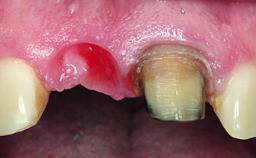

A 32-year-old female Caucasian patient with a compromised maxillary right central incisor was referred to us by a general dentist. Her chief complaints were discomfort and mobility of tooth 11 with unsatisfactory esthetics due to discoloration. The patient reported a previous trauma, some years earlier, as the origin of pathology on the afflicted tooth. Anamnesis was negative for any other dental or periodontal pathology in the remaining dentition. The patient did not take any medication and reported to be a light smoker (5–10 cigs/day). She had high esthetic expectations of her treatment. The extraoral examination revealed a high smile line with full exposure of her maxillary teeth and surrounding soft tissue in the area between the second premolars.

Soft Tissue Anatomy Intact Defective

Bone Volume Horizontally and vertically sufficient Horizontally deficient Deficient vertically or deficient vertically AND horizontally

Bone Volume Deficient horizontally, requiring prior grafting